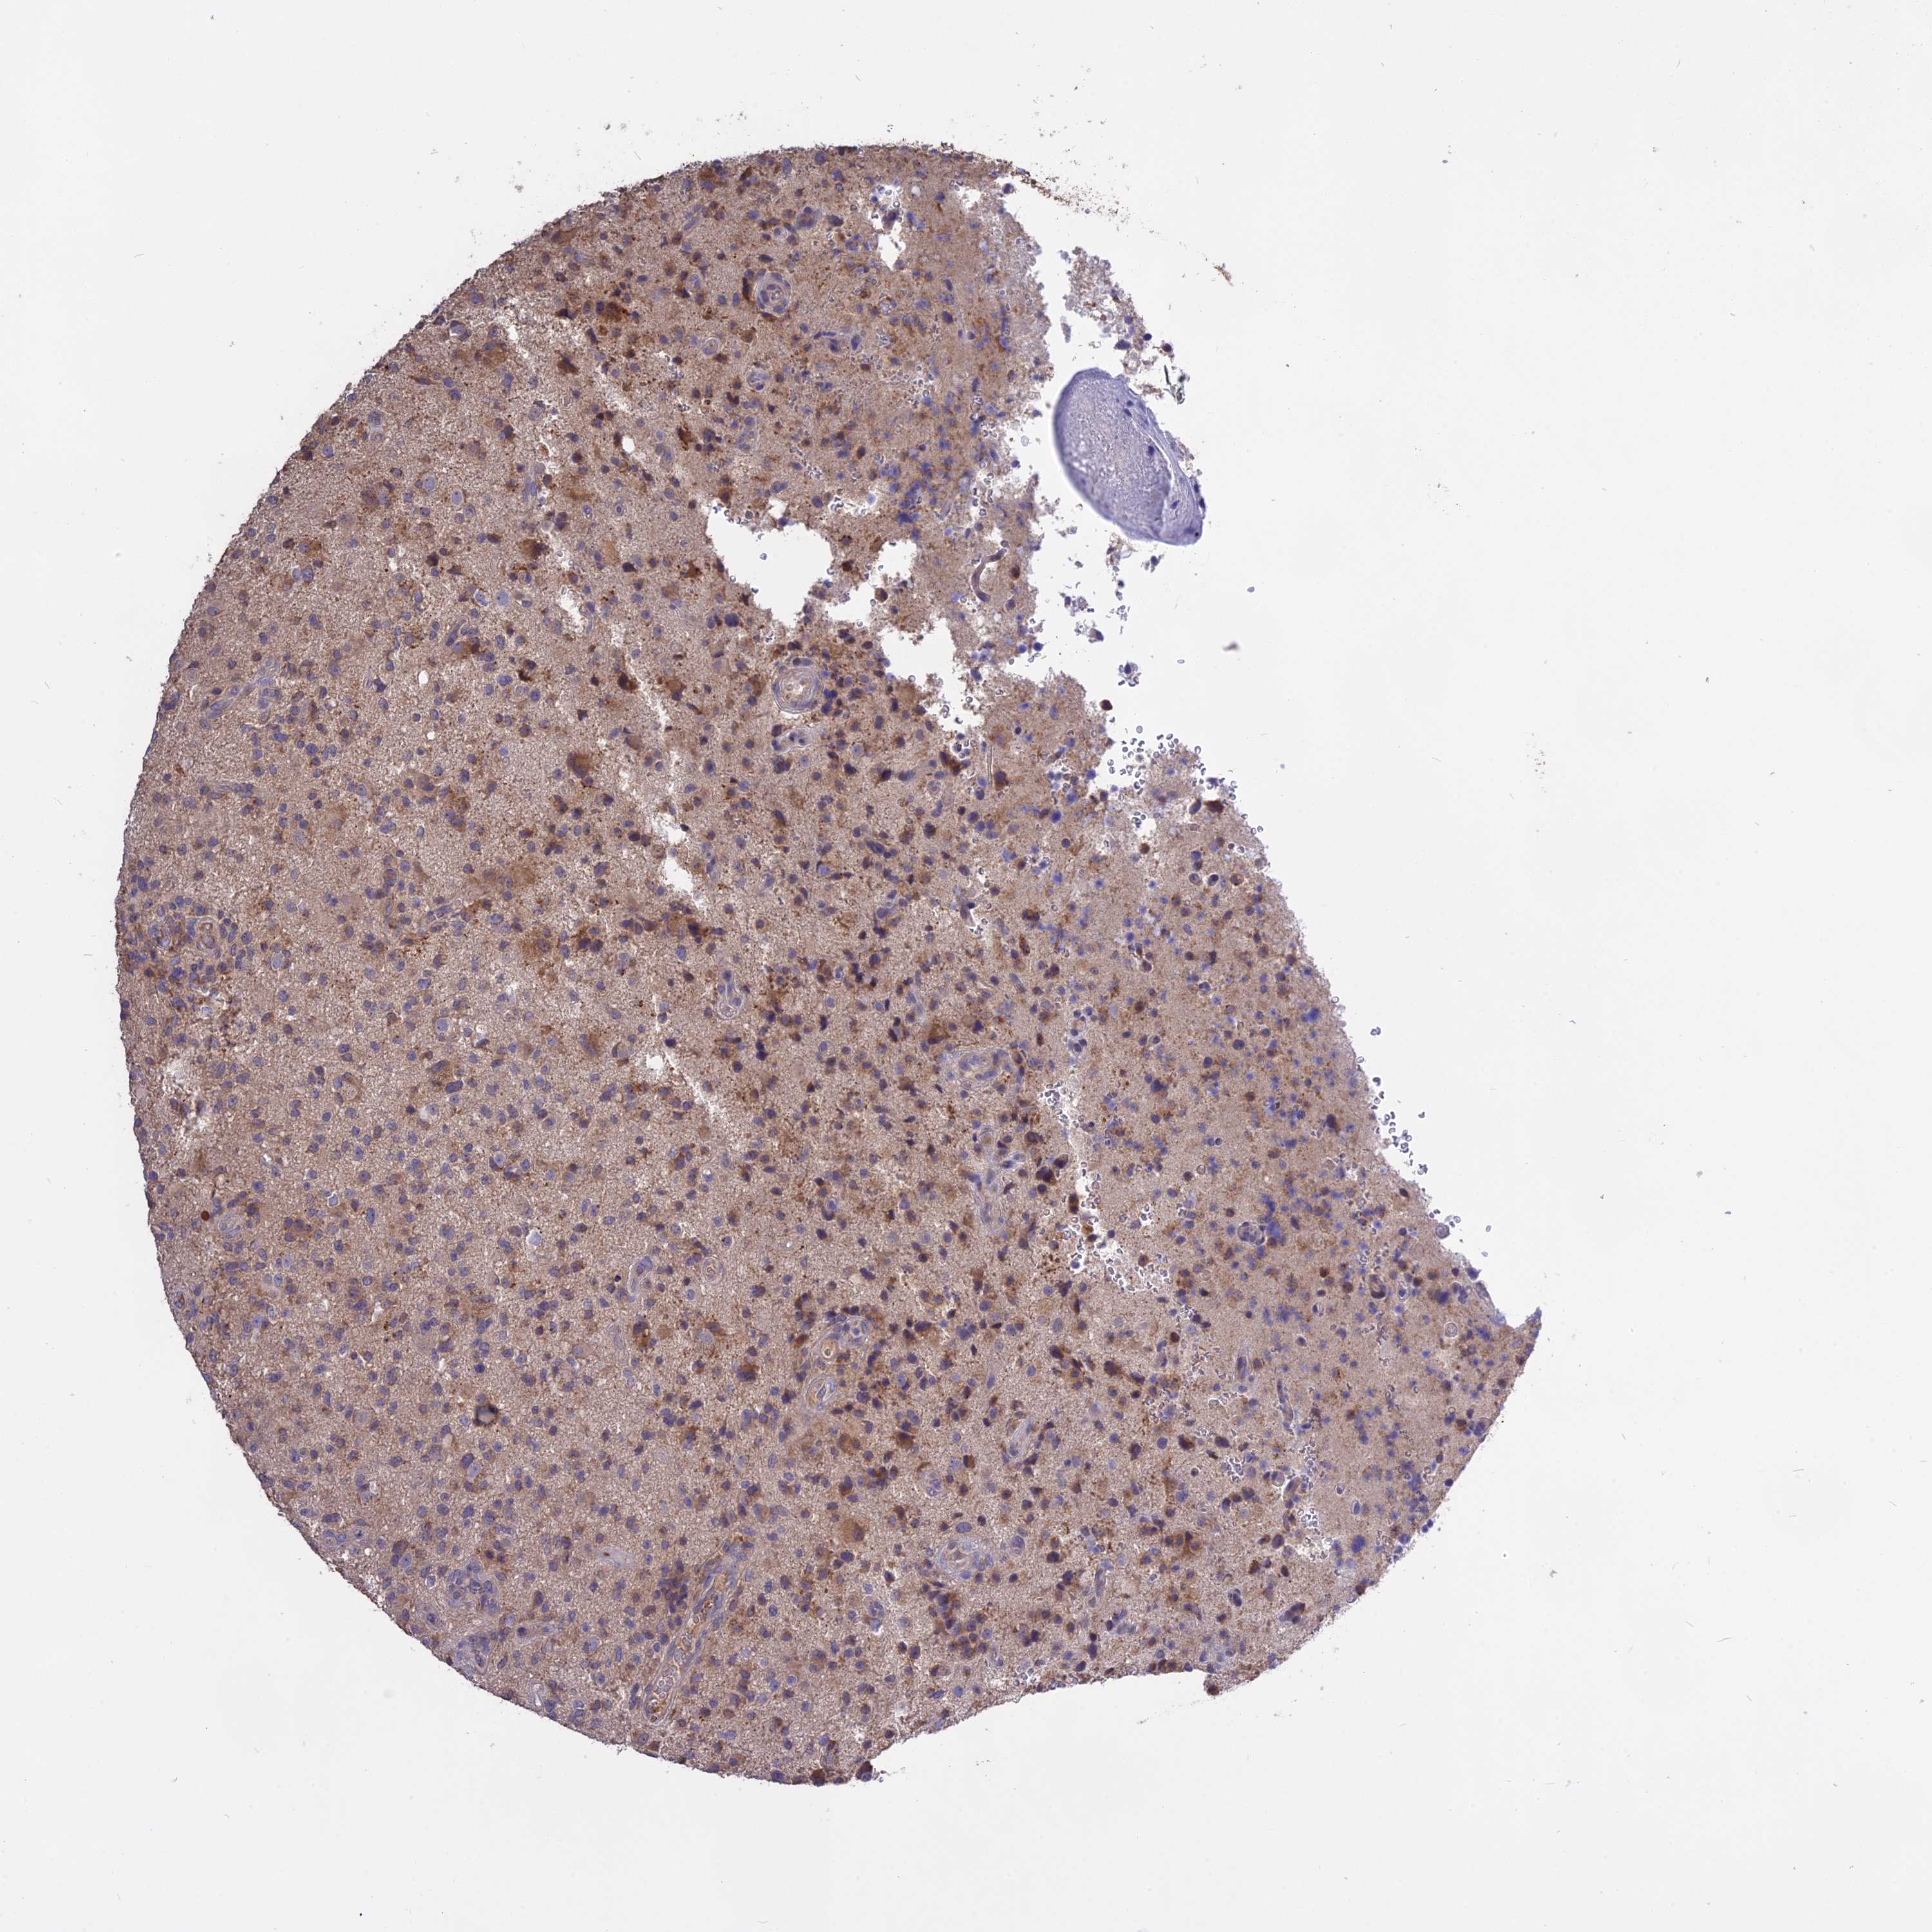

GLIOMA - Protein expressioni

A mouse-over function shows sample information and annotation data. Click on an image to view it in a full screen mode. Samples can be filtered based on level of antibody staining by selecting one or several of the following categories: high, medium, low and not detected. The assay and annotation is described here.

Note that samples used for immunohistochemistry by the Human Protein Atlas do not correspond to samples in the TCGA dataset.

Antibody stainingi

Antibody staining in the annotated cell types in the current human tissue is reported as not detected, low, medium, or high, based on conventional immunohistochemistry profiling in selected tissues. This score is based on the combination of the staining intensity and fraction of stained cells.

Each image is clickable and will lead to virtual microscopy that enables deeper exploration of all samples and also displays staining intensity scores, fraction scores and subcellular localization as well as patient and tissue information for each sample.

Antibody HPA041252

Antibody HPA041466

Glioma, malignant, High grade

Glioma, malignant, Low grade